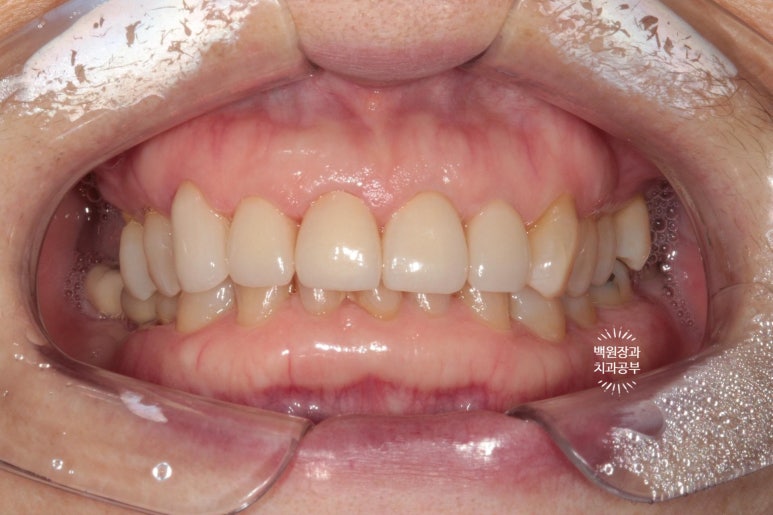

이렇게해서 두 번 수정한 앞니 지르코니아 크라운입니다.

처음에 비해 훨씬 가지런해지고 여성스러운 모양을 가진 치아로 완성되었네요!

치료 전과 후를 비교해보았을 때, 대문니에 있던 세로 금이 깔끔하게 해결되었고 밝아진 치아의 색상은 훨씬 더 환한 인상을 주게 되었습니다.

확실히 가지런해진 모습인데요, 인위적으로 색상이 밝은 것 같다고 다른 치아와 유사한 색상으로 만들어 싶어하셨어요.